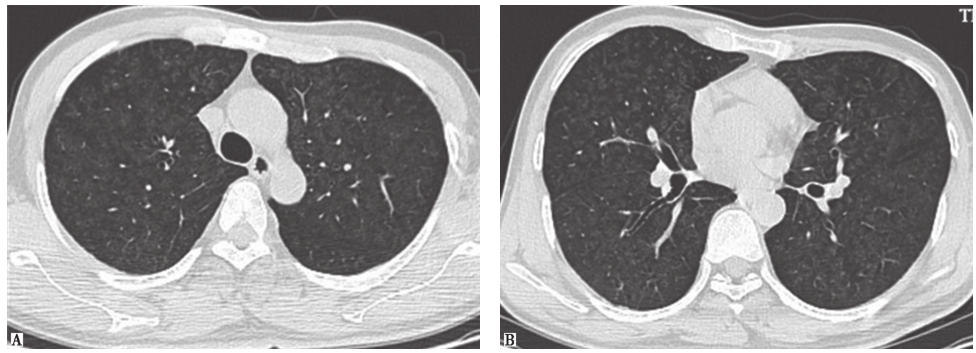

两肺散在磨玻璃影及小结节影(图13),局部网状影,较入院前(图1)明显吸收、好转。

图13入院后胸部HRCT表现

患者经泼尼松(20mg,每天2次)口服治疗,并且脱离原有工作环境,1个月后复查胸部HRCT示两肺磨玻璃影及小结节影较前进一步吸收(图17),咳嗽、气喘症状明显缓解。

图17泼尼松治疗1个月后胸部HRCT表现-6902304544819200

图17泼尼松治疗1个月后胸部HRCT表现

HRCT显示磨玻璃影及小结节影进一步减少,双肺胸膜下少量小结节影